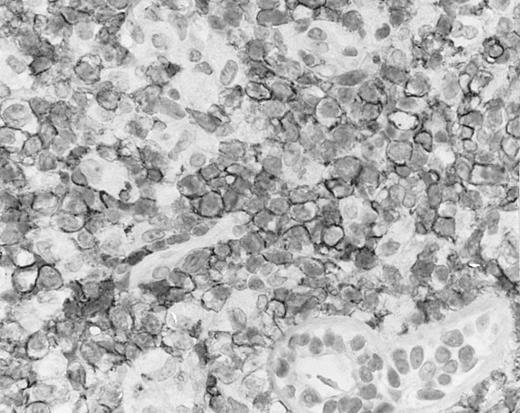

Blastoid NK cell lymphoma (case no. 40). (A) Biopsy shows a diffuse lymphomatous infiltrate with a prominent single-file pattern. (B) The neoplastic cells are medium-sized and possess fine chromatin. Mitotic figures are seen. There is remarkable resemblance to myeloid leukemic infiltration.

Blastoid NK cell lymphoma (n = 2).One patient presented with systemic disease, whereas 1 had localized disease at presentation. Histologically, the infiltrate was diffuse, with a prominent single-file pattern reminiscent of leukemia (Fig 8A). The neoplastic cells were medium-sized and had irregularly folded delicate nuclear membranes, fine chromatin, and tiny nucleoli (Fig 8B). Mitotic figures were easily identified.

In case no. 40, the immunophenotype was CD2− CD3/Leu4− CD4− CD5− CD7+ CD8− CD13− CD33+ CD56+, as analyzed on fresh tissue, and CD3ε+ (weak) CD43+ CD56+ CD68− TdT− and myeloperoxidase-negative on paraffin sections. In case no. 41, the immunophenotype as assessed on paraffin section was CD3ε+ CD43+ CD56+ TdT− and myeloperoxidase-negative. Both cases were EBERs-negative.